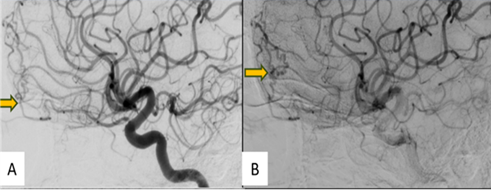

A digital subtraction angiography

(DSA) was performed for further evaluation. Right femoral access was taken with

a 5F short sheath. Selective catheterization was done and contrast was injected

into the bilateral common carotid arteries, internal and external carotid

arteries and vertebral arteries and images acquired. These revealed an anterior

cranial fossa DAVF with arterial feeders from the posterior ethmoidal branch of

the right ophthalmic artery and orbitofrontal branch of the left ACA. The

fistula drained directly into an ectatic cortical vein. No feeders could be

identified from either ECA or left ophthalmic artery (Figure 2 A & B).

Figure 2: (A) &(B) - Digitally

subtracted images through the right internal carotid artery showing anterior

the right ophthalmic artery and orbitofrontal branch of the left ACA (arrow)